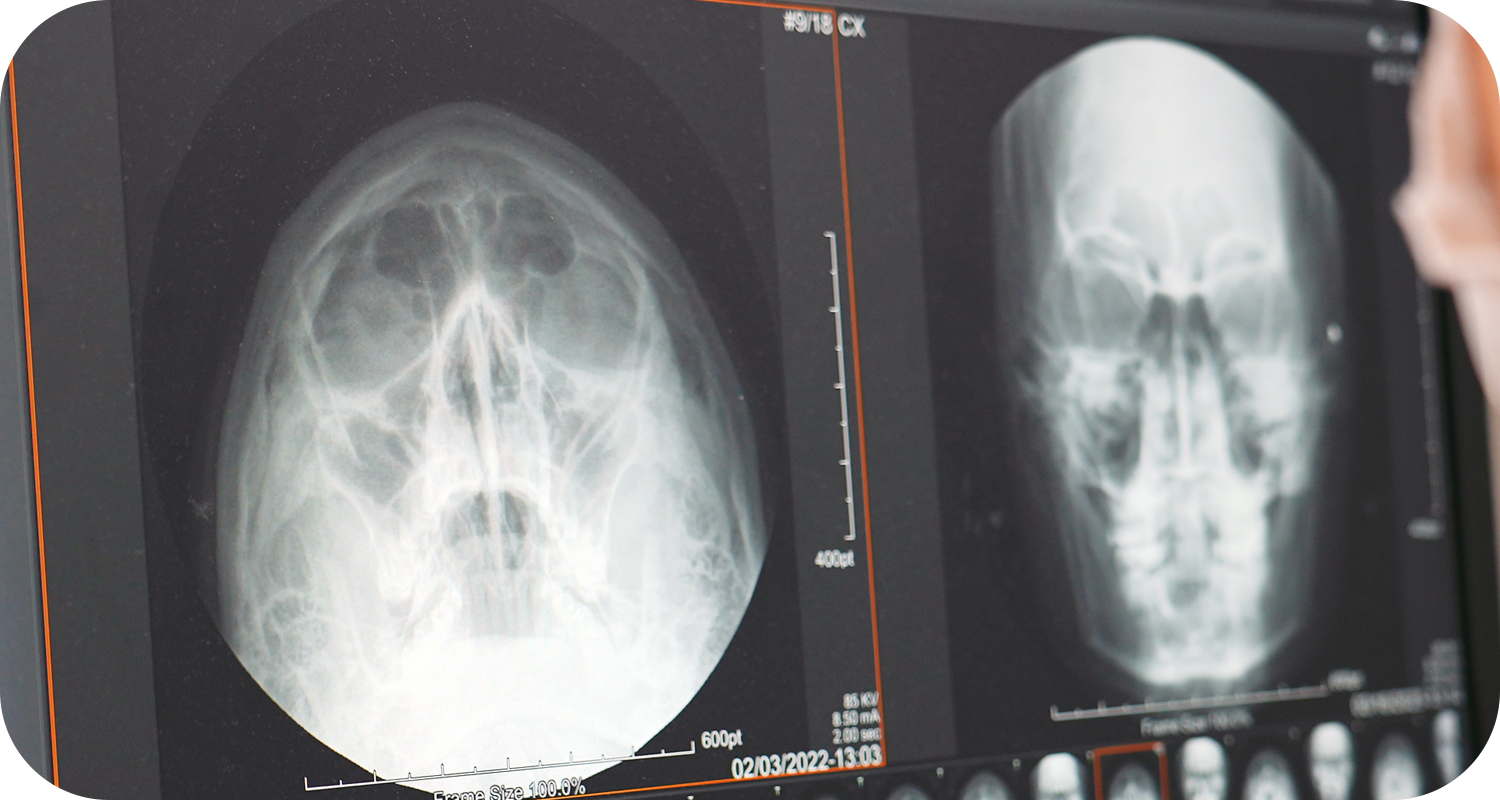

부비동 X-ray

X선을 부비동에 투과시켜

골절 여부 등을 관찰 가능

X선을 부비동에 투과시켜 골절 여부 등을 관찰 가능